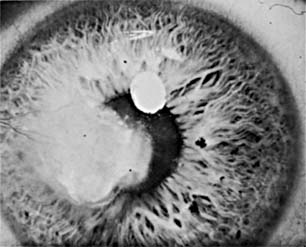

Attacks of the common recurrent type of herpetic keratitis (Figure 6-4) are triggered by fever, overexposure to ultraviolet light, trauma, psychic stress, the onset of menstruation, or some other local or systemic source of immunosuppression. Unilaterality is the rule, but bilateral lesions develop in 4-6% of cases and are seen most often in atopic patients.

Figure 6-4

Figure 6-4: Corneal scar caused by recurrent herpes simplex keratitis.

2. Lesions- The most characteristic lesion is the dendritic ulcer. It occurs in the corneal epithelium, has a typical branching, linear pattern with feathery edges, and has terminal bulbs at its ends (Figure 6-5). Fluorescein staining makes the dendrite easy to identify, but unfortunately herpetic keratitis can also simulate many corneal infections and must be considered in the differential diagnosis of many corneal lesions.

Figure 6-5

Figure 6-5: Dendritic figures seen in herpes simplex keratitis.